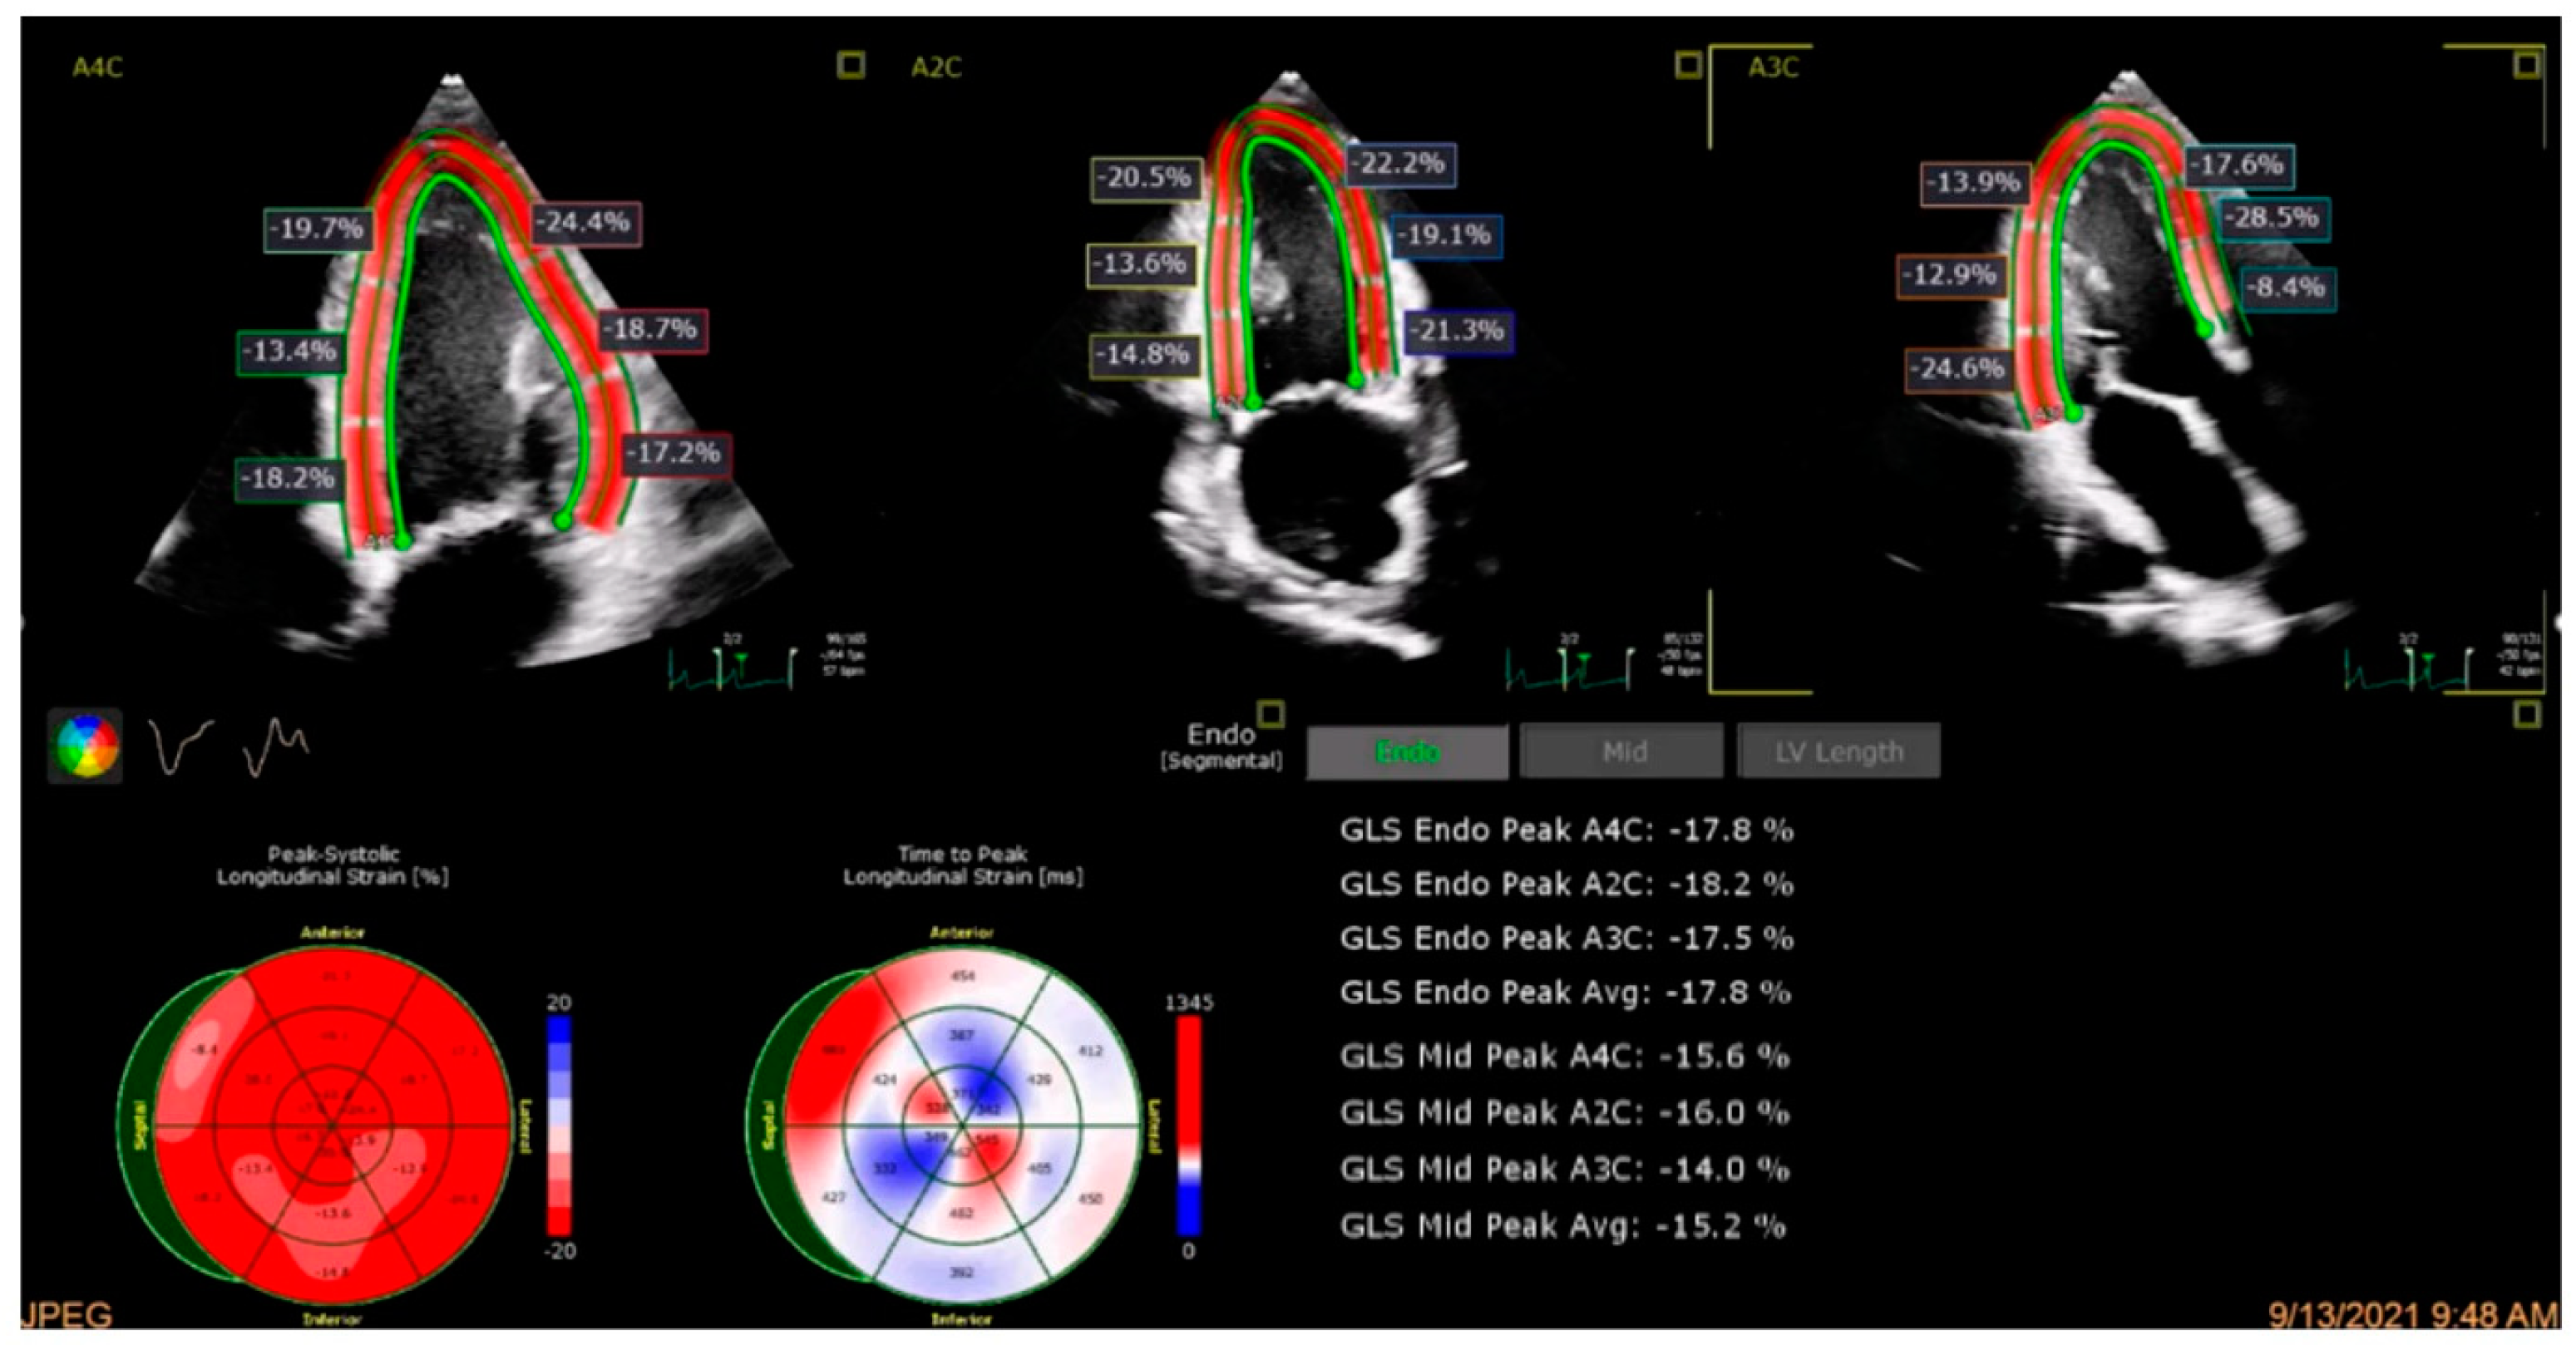

4.2. Global Longitudinal Strain